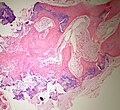

Bizarre parosteal osteochondromatous proliferation. H&E stain. | |

| LM | disorganized cellular cartilage with a blue tint and patchy ossification matures into disorganized bone, proliferation of fibroblasts surrounds the bone/cartilage and occupies the intertrabecular spaces |

Microscopic

Features:

- Disorganized cellular cartilage with a blue tint and patchy ossification matures into disorganized bone. *Proliferation of fibroblasts surrounds the lesion and occupies intertrabecular spaces.